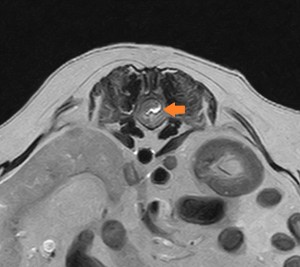

左の画像はX線写真で、左の画像はMRI検査の写真です。橙矢印が椎間板物質が飛び出していた部分ですが、X写真では脊髄の様子は分りませんが、MRI検査では脊髄が圧迫されている様子がよく分かります。

また、この画像もMRI検査の物ですが、飛び出した椎間板が造影剤で白く映し出されている様子も確認できました。